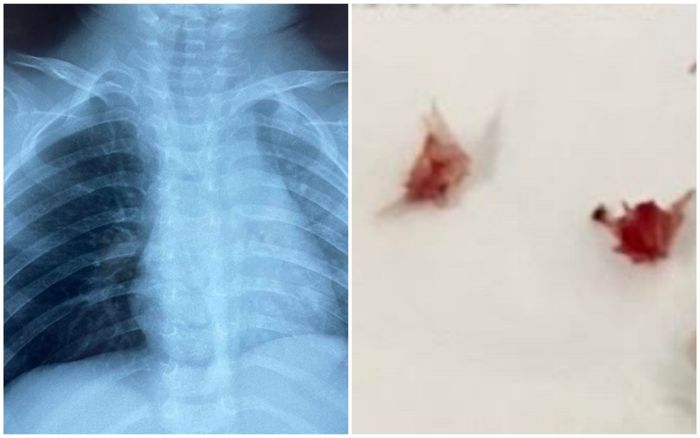

Người nhà bé cho biết, cách nhập viện 10 ngày bé đang ăn cháo lươn thì ho, sặc sụa, tím tái, được điều trị tại địa phương nhưng không đỡ, bé được chuyển đến Nhi Đồng 1 trong tình trạng khò khè, thở mệt.